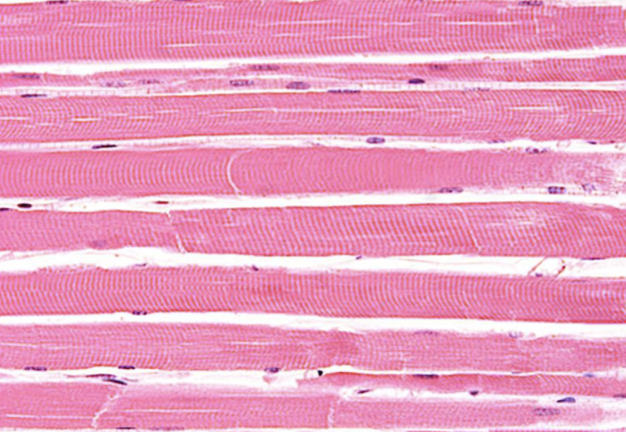

Indique tipo de tejido muscular

liso

Indique sitio anatómico donde se encuentra

organos

Indique característica propia

ausencia de estrias

Indique tipo de tejido muscular

esqueletico

Indique sitio anatómico donde se encuentra

inserto en el esqueleto

Indique característica propia

contracción voluntaria